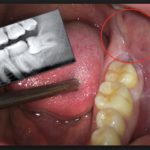

Обязателен первичный осмотр, в ходе которого делают рентген, чтобы понять, как расположен резец. Если удаление или иссечение прилегающих тканей пока невозможно, назначают гели, мази с обезболивающим эффектом. Пациенту рекомендуют взять больничный, нормализовать питание, избегая слишком горячей или холодной пищи, а также исключив твердую еду, которая еще больше травмирует ротовую полость. Но проблемное прорезывание – это практически всегда повод для удаления моляров. Выполняют его следующим образом:

Доктора предупреждают, что такие скрытые аномалии тоже опасны, потому что повреждают корневую систему соседних «семерок». Всегда необходимо сделать рентген, даже если отсутствует боль, лезет зуб мудрости в правильном положении, не причиняя неудобств, чтобы убедиться, в отсутствии опасности для «сородичей». После этого врач примет решение. Не стоит бояться походов к стоматологу, ведь все манипуляции проводятся под местной анестезией. Если лезет зуб мудрости, болит и приносит неудобства, его можно удалить. Современные технологии помогут избавиться от проблемы навсегда!